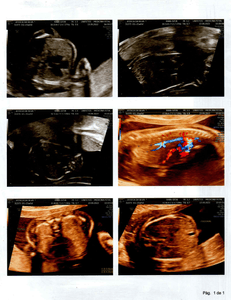

Olá amigos e amigas, eu Laidson Saturnino Souza Santos, descobri que minha filha, com idade gestacional de 21 semanas e 6 dias, foi diagnosticada com MIELOMELINGOCELE SACRAL, ESPINHA BÍFIDA OU ESPINHA ABERTA, no dia 13/09/2022, por meio de uma ultrassonografia morfológica. Ela possui uma MALFORMAÇÃO NA COLUNA. Em decorrência disto provavelmente nascerá com ANOMALIAS ESTRUTURAIS, DOENÇAS GÊNICAS, RETARDO MENTAL, CROMOSSOMOPATIAS (SINDROME DE DOWN), entre outros problemas. A única forma de tentar reverter esse problema seria uma cirurgia intrauterina, ou seja, os médicos farão uma cesárea, irão abrir o útero da mãe, chegar até meu filho, onde irão fechar a sua coluna, q está aberta. Feito isto suas chances de nascer perfeito São grandes, claro que os médicos não descartam a hipótese de haver sequelas, mas acreditamos na cura total. Se a mãe não se submeter a esse procedimento, assim q ela nascer irá pra cirurgia para fechar a coluna, mas já será tarde demais e consequentemente ficará sem andar entre outras complicações e por fim será uma menina especial pro resto da vida. Estamos aqui correndo contra o tempo, pois o prazo será até a 26ª semana, ou seja, temos 4 semanas para organizar tudo, e levantar o dinheiro. Não sabemos ao exato o quanto custa essa cirurgia, mas passa de $ 20,000 DÓLARES, aqui no Brasil. Onde moramos, Bahia, este procedimento não é realizado, só em São Paulo ou Rio de Janeiro. Então abandonaremos tudo aqui, família, amigos, ...  para tentar dar um futuro melhor para a LIZ. Estamos tentando os órgãos públicos para obtermos a cirurgia através do SUS (Sistema Único de Saúde). Mas é difícil e não temos como esperar. Então criamos uma conta para levantarmos a quantia suficiente e assim poder realizá-la. Peço que quem tiver interesse em ajudar repasse esta mensagem aos seus amigos, para juntos salvarmos a vida da minha menina.